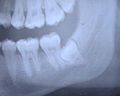

- On voit à la fois des dents temporaires et des dents définitives.

- Radiographie de dents saines (prémolaires, molaires, dent de sagesse incluse) et cariées (2e prémolaire supérieure et 1re molaire supérieure).